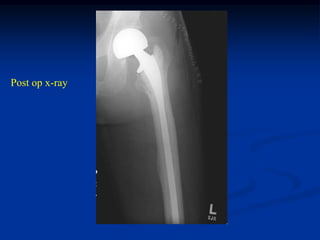

Case #1128

61 year female with metastatic renal cell CA hip area